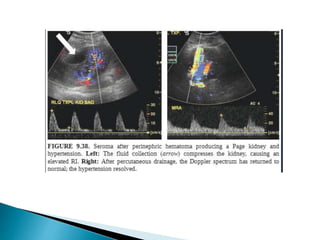

 Unusual complication.

 First 2 weeks of transplant surgery.

 Predisposing causes :- Acute rejection. ATN, vascular occlusion.

 Imaging

1. Renal parenchymal laceration

2. Intra-renal hematoma

3. Peri-renal hematoma.

1. USG:- hypoechoic fluid collection represents a hematoma within the

laceration/peri-nephric space.

2. CT:- dense clot within the laceration/peri-nephric space.